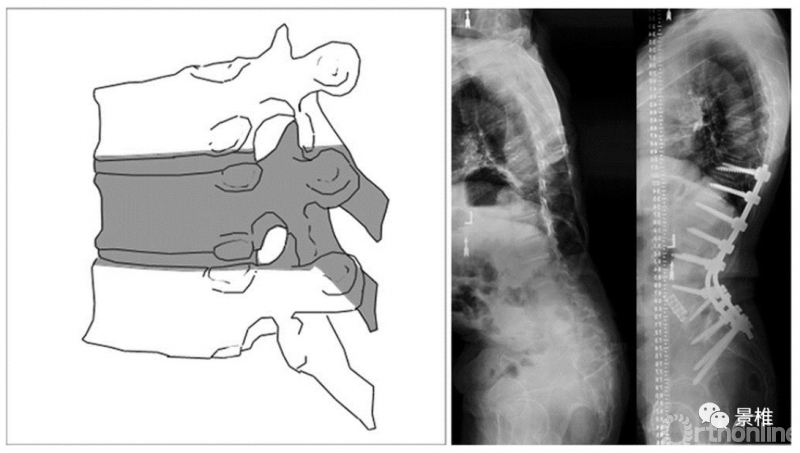

4级 BDBO

4级,更进一步,除了切部分椎体,连上/下方椎间盘都切,以获得更大的后凸矫正角度。也叫BDBO(Bone-Disc-Bone Osteotomy)。